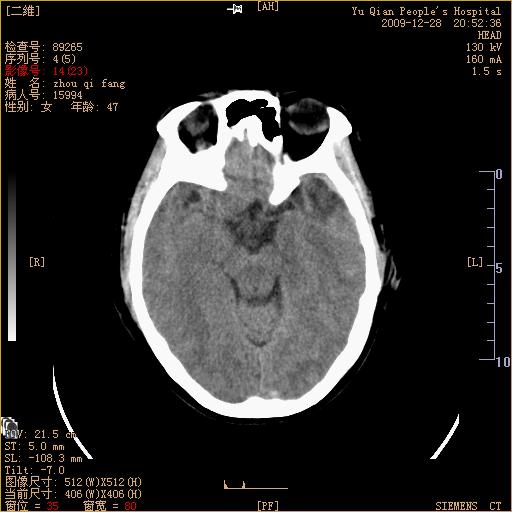

头部外伤后1天   请看看左侧丘脑外侧原是否为小血肿?(两天表现大致相仿。)谢谢

左颞叶前外部见片状挫裂伤,左丘脑小血肿;颅板下见多发小片状血肿影,两侧额部见少量蛛网膜下腔出血,

左额叶颅内板下也有一高密度灶。。。考虑多发小灶性出血(挫裂伤)。。。复查后再定

不好定。同时左侧裂池形态异常,左侧豆状核点状高密度,第四幅右额叶稍高密度影,最后一幅左额叶颅骨内板下方小片状高密度影。复查。